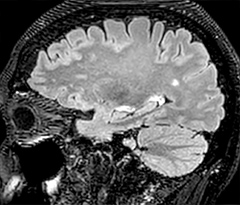

A two year follow-up scan of a CPA meningioma using both Ingenia 3.0T without CS and Ingenia Elition 3.0T with Compressed SENSE allows for a nice comparison to demonstrate the protocol improvements achieved on the Elition: 3D FLAIR has a shortened scan time, improved SNR and still the same spatial resolution. BrainView (3D T1 TSE) has improved spatial resolution and SNR with shortened scan time. For 3D T2 Drive the spatial resolution has been improved. 3D THRIVE used to have an interpolated 0.8 mm slice thickness, but true thickness at 1.6 mm, so that axial slices displayed a decent quality, but reformats were suboptimal. Compressed SENSE is used on Elition to improve spatial resolution and reduce the non-interpolated slice thickness to allow smoothly reformatted images. Total scan time (adding SmartBrain and an additional b2000 diffusion) was 13:19 on Ingenia, and is now reduced to 10:42 on Ingenia Elition.

Ingenia 3.0T (without Compressed SENSE)

3D FLAIR 1.0 x 1.0 x 1.0 mm* 4:24 min.

3D TSE T1w 1.0 x 1.0 x 1.2 mm* 2:40 min.

3D T2w Drive 0.8 x 0.8 x 1.0 mm* 3:05 min.

3D T1w THRIVE 0.8 x 0.8 x 1.6 mm* 1:30 min.

Ingenia Elition 3.0T with Compressed SENSE

3D FLAIR 1.0 x 1.0 x 1.0 mm* 2:50 min.

3D TSE T1w 1.0 x 1.0 x 1.0 mm* 2:10 min.

3D T2w Drive 0.7 x 0.7 x 0.7 mm* 2:52 min.

3D T1w THRIVE 0.7 x 0.7 x 0.8 mm* 1:30 min.

*true voxel size, without interpolation